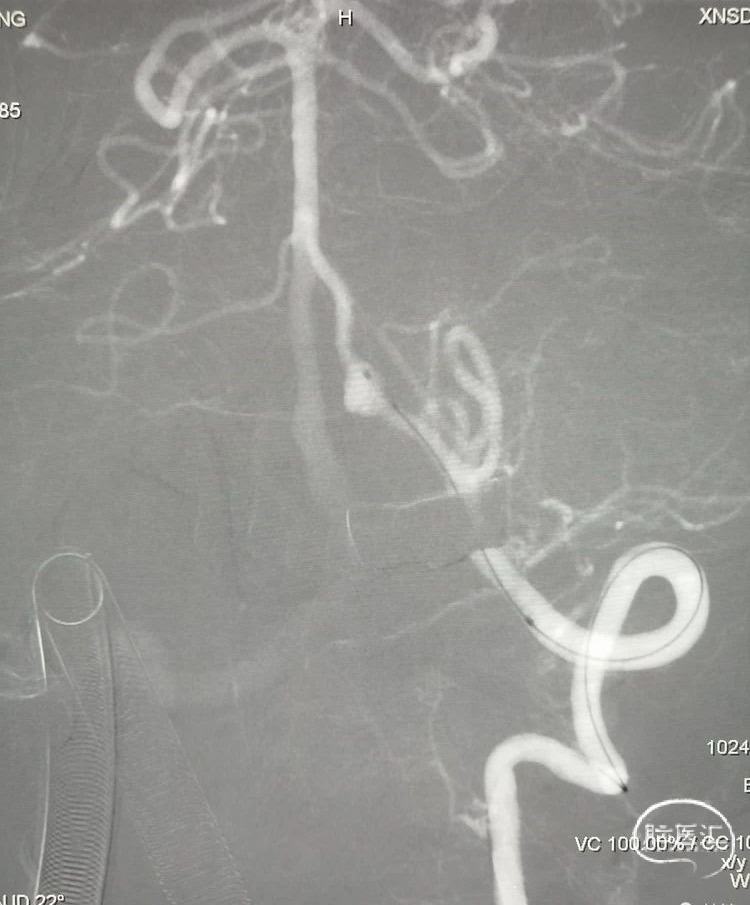

数枚弹簧圈进去,载瘤动脉及动脉瘤致密栓塞,小脑后下动脉显影良好,且有侧支与基底动脉近端联通。

术后用导引导管到右侧锁骨下动脉造影,显示右侧椎动脉、基底动脉及远端的各重要分支血流通畅,手术用时不足半小时,麻醉醒后患者无任何神经功能缺损表现,住院一周后回广东了,嘱咐患者三个月后在当地医院复查。